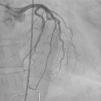

Case reportWe present the case of a 75-year-old Caucasian woman with a previous history of hypertension, dyslipidemia and a left total hip replacement. She was medicated with lisinopril-hydrochlorothiazide, bisoprolol and atorvastatin. Additionally, she was recently diagnosed with atrial fibrillation and was on warfarin. She had no previous symptoms of cardiac disease. She went to the emergency department of the local hospital due to nonspecific thoracic discomfort and malaise of over six hours duration associated with an episode of syncope. She also reported dyspnea on moderate exertion of two weeks duration. A complete blood count (CBC) and biochemistry revealed anemia and thrombocytopenia, with no other changes. The patient denied other signs or symptoms. Physical examination revealed a low-amplitude arrhythmic pulse, no heart murmurs and no signs of pulmonary congestion, blood pressure of 95/56 mmHg, heart rate of 101 beats per minute, and peripheral oxygen saturation of 85%. The CBC revealed anemia (Hg 8.9 g/dl) and thrombocytopenia (80 000 U/l). Biochemistry results revealed elevated serum cardiac troponin I (0.9 ng/ml; normal <0.04 ng/ml). A chest X-ray revealed a cardiothoracic index of >50% with widening of the mediastinum. The ECG revealed atrial fibrillation with ST-segment elevation in V2-V6, I and aVL. The patient was immediately transferred to a tertiary centre for emergent coronary angiography, which revealed a long stenosis of 50% in the mid-distal portion of the left anterior descending artery (with TIMI 3 flow) and a focal 30% stenosis in the mid segment of the right coronary artery (Figure 1). Left ventriculography revealed a hyperkinetic left ventricle and apical akinesia but otherwise normal systolic function. In the minutes after cardiac catheterization, the patient developed hypotension (systolic blood pressure of 85-90 mmHg) and slight chest discomfort persisted. An echocardiogram was performed and revealed a large pericardial effusion with diffuse thickening of the myocardium, mainly in the anterolateral wall and apex, which was assumed to be adherent fibrin (Figure 2). Due to worsening hemodynamic status and echocardiographic findings in a patient with chest pain, ST-elevation on the ECG and elevated cardiac troponin, cardiac rupture was suspected and the patient underwent urgent sternotomy and pericardiotomy with drainage of a large quantity of bloody fluid followed by hemodynamic recovery. The surgeons then identified a large unresectable tumor occupying the distal half of the anterior portion of the heart, which was biopsied (Figure 3). The patient was admitted to the cardiothoracic intensive care unit and was extubated on day 2 after surgery, and was then transferred to an intermediate care unit, with a favorable clinical status. A cervical-thoraco-abdominal-pelvic computed tomography (CT) scan was performed that identified myocardial tumor infiltration (measuring 6 cm×7 cm×11 cm) and pulmonary, cervical and abdominal wall metastases. The pathological study revealed a malignant mesothelioma. The immunohistochemical study documented diffuse expression of AE1/AE3, vimentin and MDM2 in tumor cells and focal expression of calretinin, EMA, podoplanin, desmin and p53 (Figure 4).